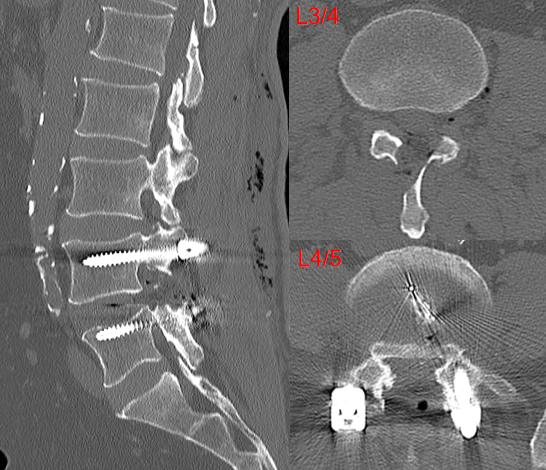

病例(减压不彻底,椎间盘残留)

男,73岁。

主诉:腰痛2年、加重伴右下肢疼痛麻木4个月,右足底、小腿后外侧为著。

术后右下肢症状无明显改善

思考和建议

减压区域应达到椎弓根中段,侧隐窝、椎间隙以及椎间孔内部3个区域都应充分减压